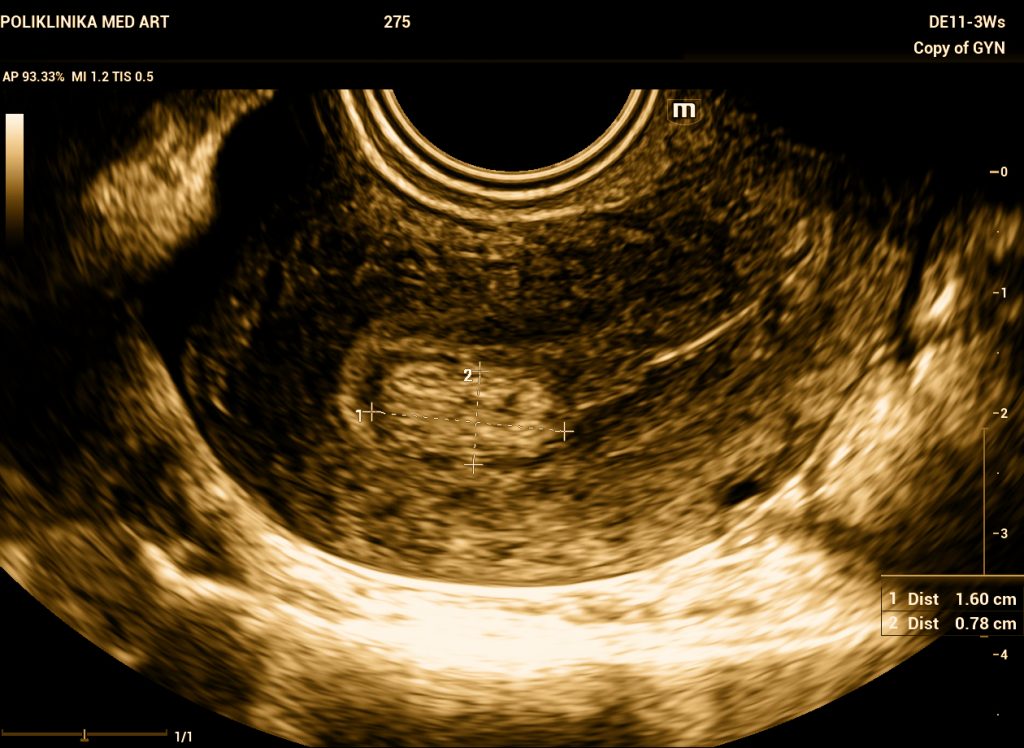

Fotografija: Ultrazvučni prikaz polipa u maternici

Razlika između dobroćudnog polipa i maligne tvorbe se može odrediti jedino patohistološkom analizom, što znači da je potrebno polip ukloniti i poslati patologu koji će odrediti o kakvoj vrsti promjene se radi. Ultrazvučnim pregledom se može postaviti sumnja na malignu promjenu ako je tvorba velika, nepravilnog izgleda, ima nepravilne rubove, obilnu prokrvljenost s više žila hranilica. No, ultrazvuk nije dovoljan za definitivnu dijagnozu radi li se o dobroćudnoj ili zloćudnoj tvorbi. Nije nužno kod svakog polipa ići na operaciju, može se planirati ultrazvučno praćenje ako tvorba ne izgleda sumnjivo.

Polip na maternici se dijagnosticira ultrazvučnim pregledom. No, to nije definitivna dijagnoza – definitivna dijagnoza se postavlja kad se ukloni tvorba i patohistološki analizira.

Postoji pretraga koja se zove sonohisterografija (SIS). To je ultrazvučna pretraga prilikom koje se u maternicu ubrizga fiziološka otopina da bi se poboljšala vizualizacija. Koristi se kad se ne može prikazati točan oblik tvorbe te utvrditi jasna granica između tvorbe i sluznice maternice.

Ultrazvučni prikaz tvorbi u maternici

| vrsta tvorbe | obrazac krvarenja | oblik tvorbe | color doppler | boja tkiva na ultrazvuku | tvrdoća tkiva |

| polip na maternici | pojačano menstrualno krvarenje i sukrvica unutar ciklusa | ovalna tvorba jasnih granica | jedna pravilna žila hranilica koja ulazi u polip | iste boje kao i sluznica maternice -bjelkaste boje | mekan, ali kompaktan i može se ukloniti u cijelosti |

| miom | pojačano menstrualno krvarenje i sukrvica unutar ciklusa | okruglasta tvorba jasnih granica | pravilan periferni protok oko mioma | tamniji od sluznice maternice, sjena iza mioma | tvrd i čvrst, može se ukloniti u cjelosti |

| karcinom | vrlo nepravilno, jače i učestalo krvarenje | nepravilna tvorba nejasnih granica prema okolnim strukturama | više nepravilnih krvnih žila koje ulaze u tvorbu, jaka prokrvljenost tvorbe | tkiva različite obojenosti unutar strukture, nema pravila | rasipa se prilikom otklanjanja, histeroskopija nije definitivna operacija |